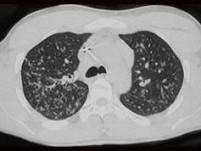

问题 男,26岁,发热,夜间盗汗,咳嗽半月余,请结合CT检查选出最可能的诊断 ( )

选项 A、肺转移瘤 B、矽肺 C、间质性肺炎 D、弥漫型肺癌 E、粟粒型肺结核

答案 E